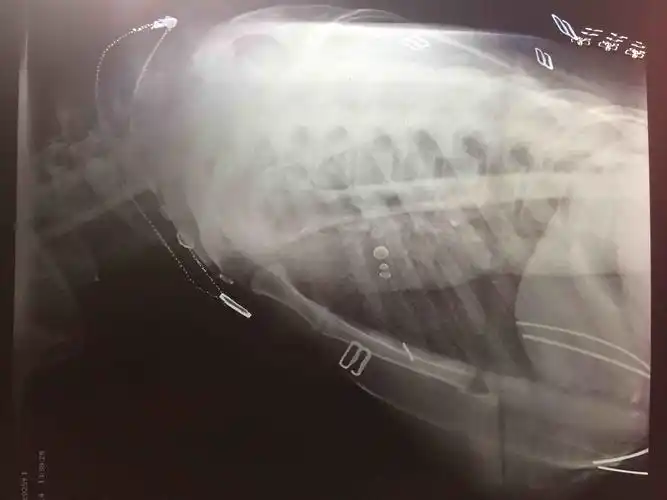

直举性肱骨脱位:罕见的肩关节脱位,肱骨头向下异位,而胳膊上举.